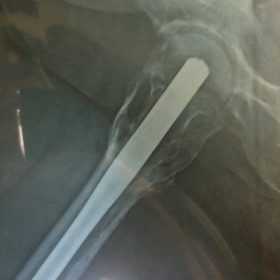

Διατροχαντήριο : Εξωαρθρικό κάταγμα, στην περιοχή ανάμεσα στο ελάσσονα και το μείζονα τροχαντήρα. Αντιμετωπίζεται χειρουργικά με ενδομυελική ήλωση τύπου γ-Nail. Δύο τομές 3 εκατοστών και 1 εκατοστού αντιστοίχως για την εισαγωγή και το κλείδωμα του ήλου μέσα στο οστό. Η μέθοδος είναι κλειστή,σχεδόν αναίμακτη,διάρκειας 30 λεπτών,με τη βοήθεια C-ARM (τηλεόρασης). Στον ασθενή παρέχεται οπτικό υλικό (όλα τα χειρουργικά στάδια) σε CD ή Στικάκι,λόγω της δυνατότητας καταγραφής του χειρουργείου από το C-ARM Ο ασθενής περπατάει άμεσα μετεγχειρητικά στις 5 ώρες μετά την επέμβαση και εξέρχεται από το νοσοκομείο σε 1 -2 ημέρες.